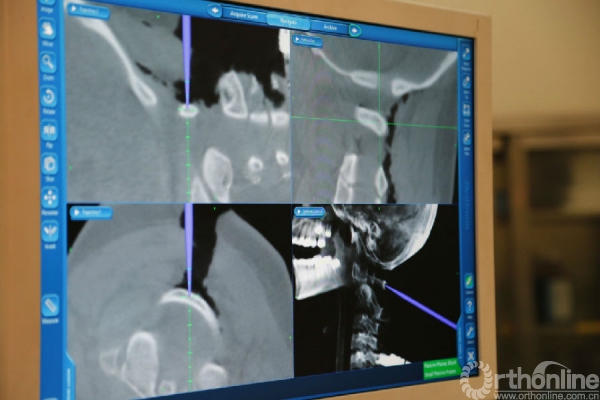

患者杨静(化名)15岁,发现颈椎先天性畸形10余年,持续的多年支具外固定,活动后颈部疼痛,严重影响生活,后慕名到西京骨科医院就诊。入院后由桑宏勋副主任为其进行了全面病情评估,发现患者寰枢椎畸形严重,并伴有椎动脉高跨,病情复杂手术风险大,经过科室讨论决定为其实施“导航辅助下寰枢椎脱位复位、椎弓根螺钉内固定、植骨融合术”。术中利用O-arm扫描获得患者实时影像数据,导入导航系统进行三维重建后进行精准的置钉、复位等手术操作。相对于传统手术方式,O-arm联合导航系统可以使手术操作可视化、精准化,减少手术时间与术中出血量,降低患者手术风险。术后患者恢复良好并已康复出院。

术中影像图片